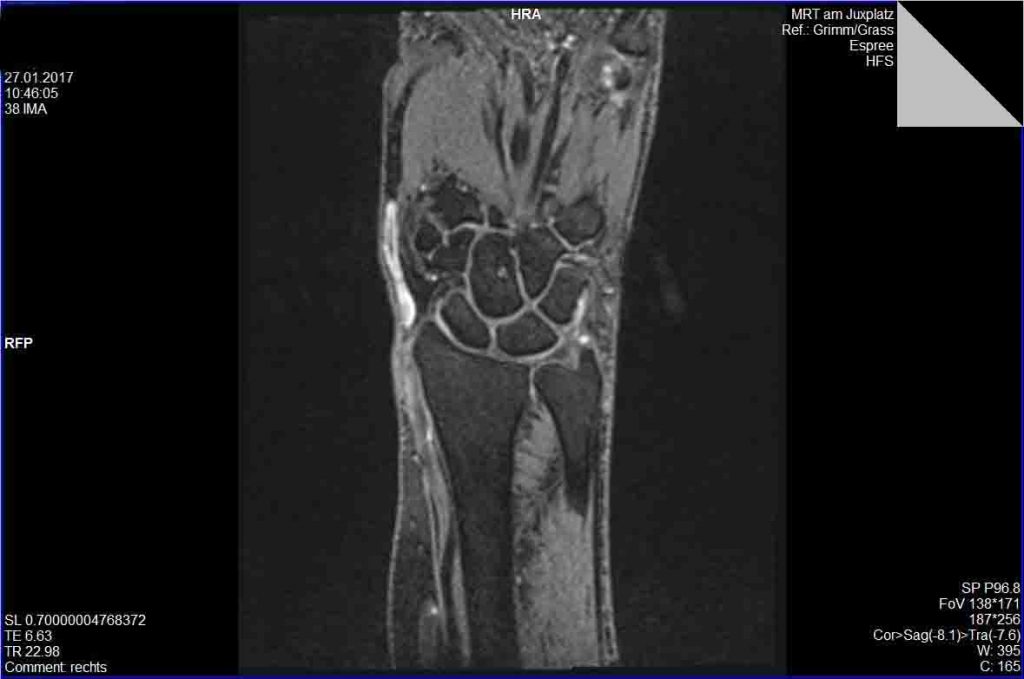

De Quervain

De Quervain's Tenosynovitis Denver, Colorado — Dr. Nick Golinvaux from www.nickgolinvauxmd.com

De Quervain's Tenosynovitis Denver, Colorado — Dr. Nick Golinvaux